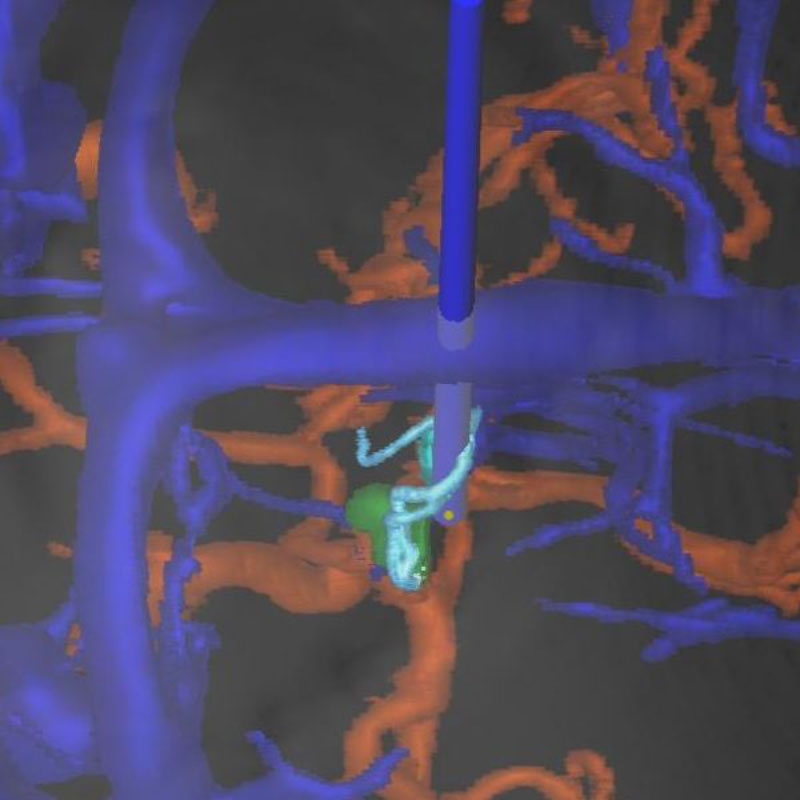

脳血管撮影

手術前

手術後

手術中

手術写真